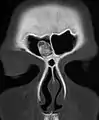

An osteoma (plural osteomas or less commonly osteomata) is a new piece of bone usually growing on another piece of bone, typically the skull. It is a benign tumor.

Osteoma represents the most common benign neoplasm of the nose and paranasal sinuses. The cause of osteomas is uncertain, but commonly accepted theories propose embryologic, traumatic, or infectious causes. Osteomas are also found in Gardner's syndrome. Larger craniofacial osteomas may cause facial pain, headache, and infection due to obstructed nasofrontal ducts. Often, craniofacial osteoma presents itself through ocular signs and symptoms (such as proptosis).[2]